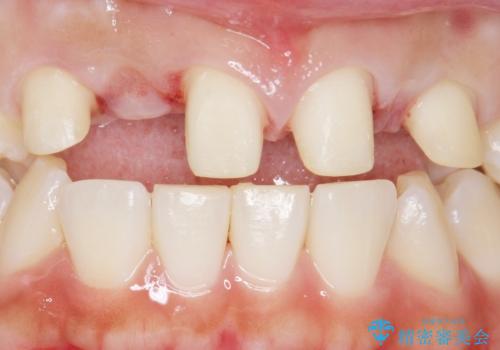

矯正以外の治療法で早く治したいとのご希望により、上顎両側犬歯を抜去しオールセラミックのブリッジによる補綴治療を行いました。

- ¥660,000 (仮歯×6本、クラウン×6本)費用は治療当時の料金となります